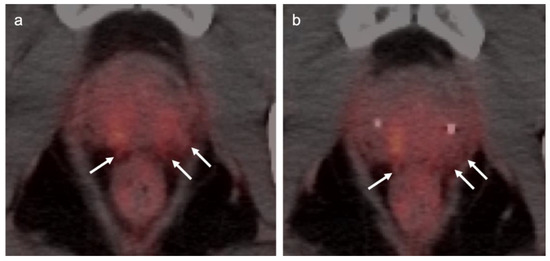

3.1. Prostate Cancer